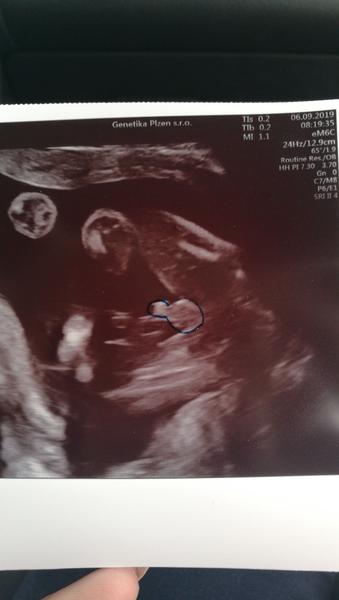

@laloogrey no ahoooj, krasne zpravy...ja byla vcera na kontrole, take vse ok, a priklani se stale k chlapeckovi🙂 strasne se tam pletl pupecnik, tak budeme muset pockat na uplne potvrzeni na druhou genetiku 🙂 take uz mam 4 dny pohyby,vecer v klidu...akorat ta vaha, 18tt a + 4kg, nekdy 4,5....des🙂 s malou jsem v tomhle tydnu mela jen 2....🙂

@laloogrey @1leny jj ono se to nejak srovna snad..zacinam 19tt a 59kg,takze +4....s malou to bylo o kilo a pul mene,ale co,taky je to vlastne treti tehu,nevolnosti jsem nikdy zadne nemela,takze na.to ze jim vic hned od zacatku pohoda😉no jsem zvedava jestli dostanu na genetice fotku pindi😂😂je tajemnej ten.nas chlapecek...s nakupama ted trosku brzdim teda,dokud mi pohlavi nepotvrdi...tak 6.9.jdem..a co vy, jdete taky na druhy screening?u nas se plati tisicovka plus dalsi tisic ze chci video,kde jsou i rysy oblicejiku❤❤a pohyby mam uz od 16+3....u prvniho mas cas,to jsem mela az 20+2💋

Ahojky holky, tak u nás na druhem screeningu vsechno na jednicku🙂 Mame na 100% pindu pry🙂 tak uz tomu zacinam verit teda🙂 akorat byl celou dobu v poloze sklapovacka, nohy i ruce pred oblicejem, takze rysy smolik a jsme preobjednani na ten 25tt, tak doufam, ze to bude spolupracovat🙂 🙂